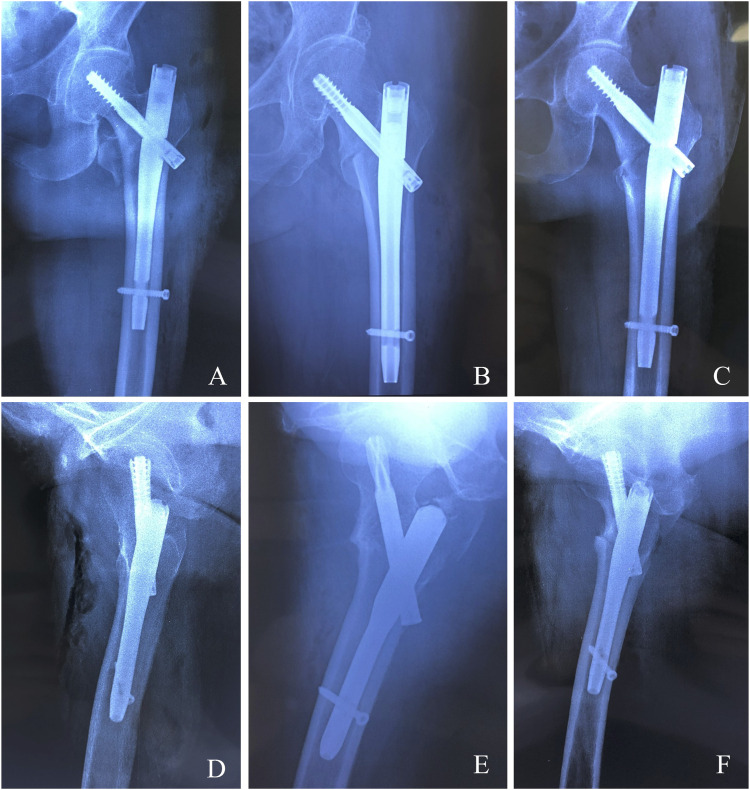

目的:利用三维(3D) CT成像定量分析股骨粗隆间骨折髓内钉内固定后的旋转位移,分析相关危险因素,并评价其临床意义。方法:本研究纳入了2019年至2023年期间接受股骨粗隆间骨折髓内钉固定治疗的252例患者。所有参与者术后接受三维计算机断层扫描(3D CT),随访至少1年。术后对患侧股骨前倾进行定量评估。分析其与潜在危险因素的相关性,包括年龄、性别、体重指数(BMI)、美国麻醉学会(ASA)分级、甲长、内固定类型、复位质量、AO基金会/骨科创伤协会(AO/OTA)骨折分型、有无内侧皮质缺损、骨矿物质密度(T-score)、Singh指数、相对外侧壁厚度(rLWT)、尖端距离(TAD)、颈轴角、以及骨折分类。通过随访评估前倾的差异对长期临床结果的影响,包括视觉模拟量表(VAS)疼痛评分和Harris髋关节评分(HHS)。结果:筛选排除标准后,共有210例患者入组研究:33例(15.7%)患者前倾差异超过15°;15°以下177例(84.3%)。在版本偏差为2.5的亚组中,rLWT和骨折分类被认为是导致旋转位移超过15°的主要因素。在1年的随访中,旋转位移较小的患者表现出更好的功能恢复,这可以通过改善的视觉模拟量表(VAS)疼痛评分和Harris髋关节评分(HHS)来反映。多元线性回归分析显示,髓内钉固定后rLWT与骨折碎片旋转位移有显著相关性。结论:股骨粗隆间骨折髓内钉固定后常发生骨旋转移位。rLWT与这些并发症密切相关。因此,对手术技术的细致关注对于减少并发症和优化结果至关重要。

Methods: This study enrolled a cohort of 252 patients who underwent intramedullary nail fixation for intertrochanteric femoral fractures between 2019 and 2023. All participants underwent postoperative three-dimensional computed tomography (3D CT) and were followed for a minimum of 1 year. Postoperative femoral anteversion on the affected side was quantitatively assessed. An analysis was conducted to evaluate its correlation with potential risk factors, including age, sex, body mass index (BMI), American Society of Anesthesiologists (ASA) classification, nail length, type of internal fixation, reduction quality, AO Foundation/Orthopaedic Trauma Association (AO/OTA) fracture classification, presence of medial cortical defect, bone mineral density (T-score), Singh's index, relative lateral wall thickness (rLWT), tip-apex distance (TAD), neck-shaft angle, and fracture classification. The impact of differences in anteversion on long-term clinical outcomes, including Visual Analog Scale (VAS) pain scores and Harris Hip Scores (HHS), was assessed through follow-up evaluations.

Results: After screening for exclusion criteria, a total of 210 patients were enrolled in the study: 33 patients (15.7%) exhibited differences in anteversion exceeding 15°; 177 patients (84.3%) were under 15°. In the subgroup with version deviations <15°, precise anatomical restoration (anteversion ≤5°) was achieved in 138 cases (77.9%), consistent with optimal biomechanical reconstruction targets; functionally compensated malrotation (5° < anteversion <15°) occurred in 39 patients (22.1%), within the tolerance range for gait adaptation without clinical impairment. Single-nail fixation, medial cortical defects, T-score >2.5, rLWT and fracture classification were identified as the primary factors contributing to rotational displacement exceeding 15°. At the 1-year follow-up, patients with smaller rotational displacement demonstrated better functional recovery, as reflected by improved Visual Analog Scale (VAS) pain scores and Harris Hip Scores (HHS).The multivariate linear regression analysis demonstrated that the rLWT showed significant correlation with rotational displacement of fracture fragments after intramedullary nail fixation.

Conclusion: Bone rotation and displacement are frequently observed following intramedullary nail fixation for intertrochanteric fractures. The rLWT is closely associated with these complications. Therefore, meticulous attention to surgical technique is essential to minimize complications and optimize outcomes.